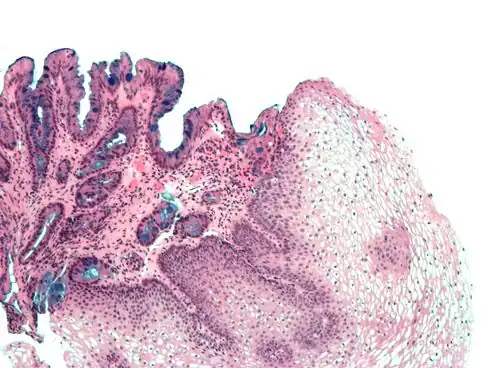

[Micrograph] of normal stratified squamous epithelium and the metaplasic epithelium of Barrett's esophagus (left of image). Alcian blue stain. -